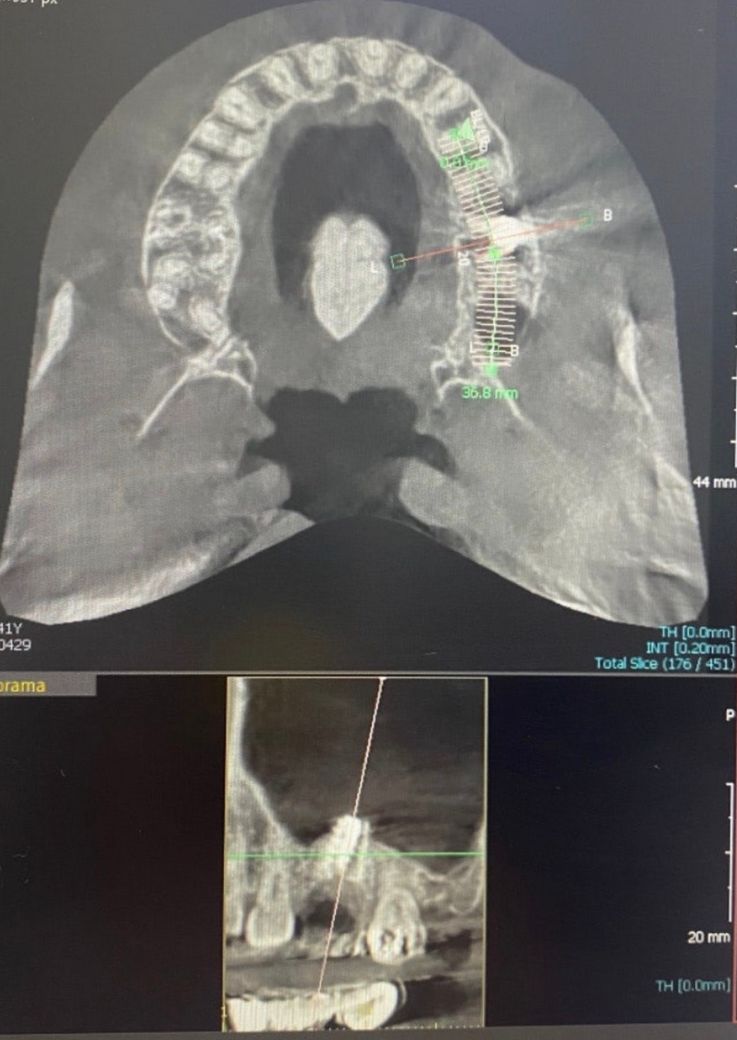

임플란트 저번엔 바깥쪽에 치우쳐서 식립 해서 염증 생겨서 결국은 빼고 3개월있다 오늘 식립했는데요 이번엔 안쪽에 치우쳐서 식립 됳어요 ㅠㅠ 오늘까지 재식립 하느라고 1년 3개월이 걸렸습니다, 작년에도 임플란트가 치우치다보니 공간부족으로 음식물이 끼고 받는 힘압력이 치우치니 염증으로 결국 다 마무리하는 시점에서 빼고 재식립 했거든요 ㅠㅠ 작년에 환불받고 다른곳에 갈껄 후회막심입니다 , 첫번빼 사진이 작년 두번째사진이 오늘입니다 임플란트가 위치가 상관 없는게 맞는가여? 3번 재식립하면 체력바닥날거 같아요 , 말도 안되구여 ㅠㅠㅠ

• 1번 째 사진

• 2번 째 사진

역학적인 관계에서 현재 위치에 식립하는 것은 크게 문제가 되지는 않습니다. 물론 이상적인 위치에 식립하면 좋겠지만 뼈와 주변 상태에 따라서 비껴 심는 경우는 워낙 많습니다. 다만 과거와 달리 임플란트 상부 보철물 중에서 중간 기둥은 맞춤형으로 들어가는 경우가 많아 이때 위치를 정상적으로 바로잡을 수 있어 크게 걱정하지 않아도 됩니다. 지금 사진에서는 치우쳐 심어서 문제가 되었다기보다는 감염이 있었을 가능성이 커보이네요.